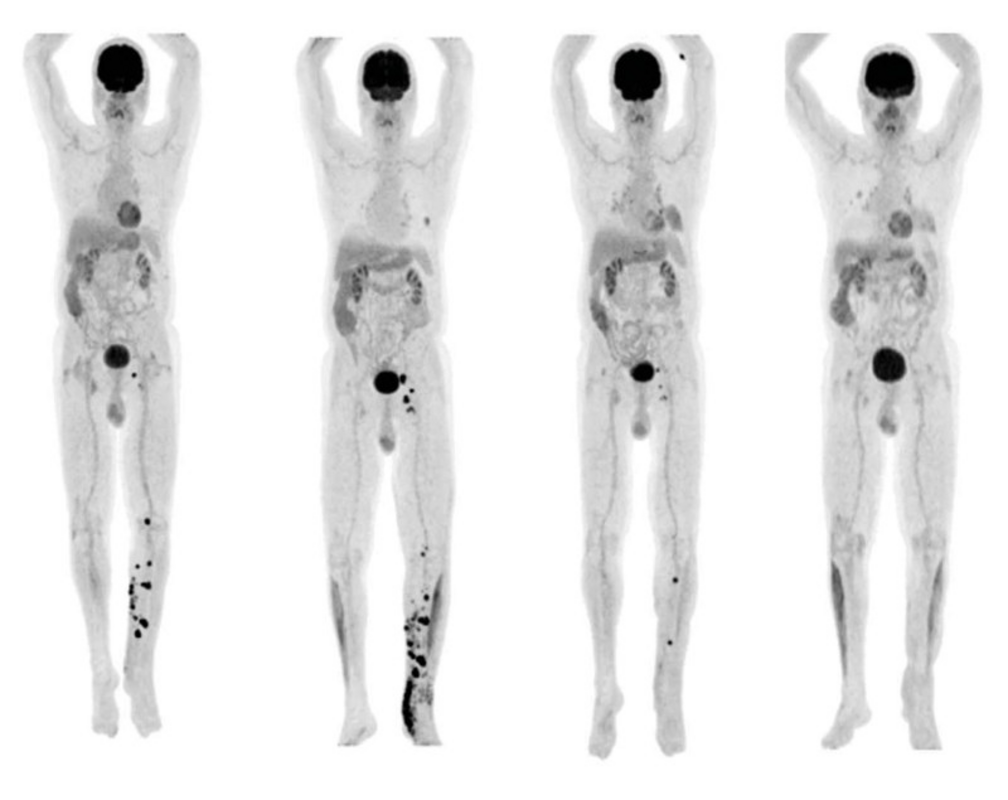

На снимках одного из участников испытания в Израиле видно, что метастазы полностью рассасываются после лечения. E. N. Baruch et al./Science

Сион Леви помнит волнение, которое он и его дочь испытывали, просматривая его в 2019 году, наблюдая, как маленькие черные точки, отражающие метастазы меланомы, уменьшаются и в конце концов исчезают.

Там фекалии Леви проверили на наличие патогенов, разбавили, гомогенизировали, центрифугировали и отсеяли до очищенного микробного бульона, который можно было высушить и упаковать в капсулы. Энтузиазм Леви по отношению к проекту убедил Бена Бурси, онколога из Медицинского центра Шиба, который возглавлял исследование, поделиться анонимными снимками человека, получившего пожертвованные им микробы. Сегодня этот человек уже более трех лет живет без признаков рака и стал донором в аналогичном исследовании по лечению меланомы. Это наследие, которым Леви очень доволен. "Я очень горжусь тем, что смог спасти жизни людей. Я бы хотел сделать это снова", - говорит он.